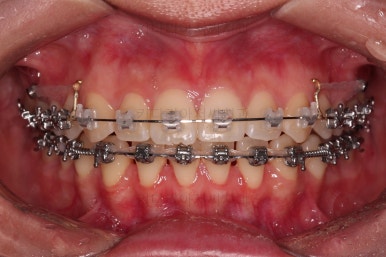

장치를 부착했는데요.

윗니는 웃을 때 더 많이 보이기 때문에 세라믹 장치를 선택하셨고, 아랫니는 거의 안보이는 타입이셔서 메탈장치로 부착을 했습니다.

위아래 둘 다 자가결찰 장치였고요.

동일 회사의 장치였으며 단지 재질만 메탈이냐 세라믹이냐의 차이가 있었던거죠.

이렇게 위아래는 설측이든 뭐든 메탈이든 세라믹이든 마음대로 섞을 수 있습니다.